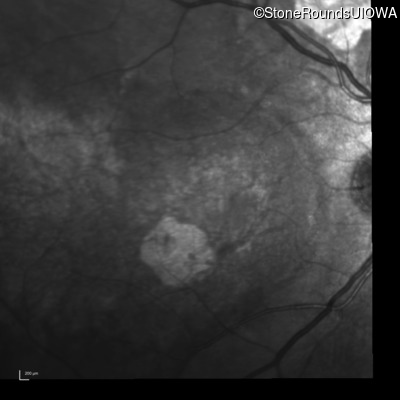

Infrared Fundus Photograph - Right - 20/100

Exemplar